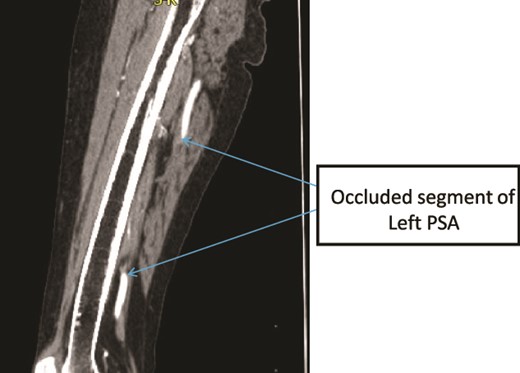

A 60-year old known psychiatric female patient presented with left LL pain and swelling for 1 week. She had claudication for 1 year and 4 months prior to presentation, she had fifth toe amputation after developing ulceration. On examination, all distal pulses were absent in the affected limb which was cold, with tender calf muscles and absent motor and sensory function. Patient was not cooperative for gluteal area examination. CTA showed bilateral prominent internal iliac arteries (IIAs), bilateral PSAs with left PSA fusiform aneurysm with surrounding thrombus, and no signs of rupture (Fig. 7) There was also central filling defect occluding the left mid-thigh PSA and left PA (Figs 8 and 9) With a diagnosis of Class III acute limb ischemia, the patient was offered surgical amputation but refused and was discharged against medical advice.

Case 3—sagittal images of LL CTA of the left LL arteries showing occluded left PSA in the mid-thigh.